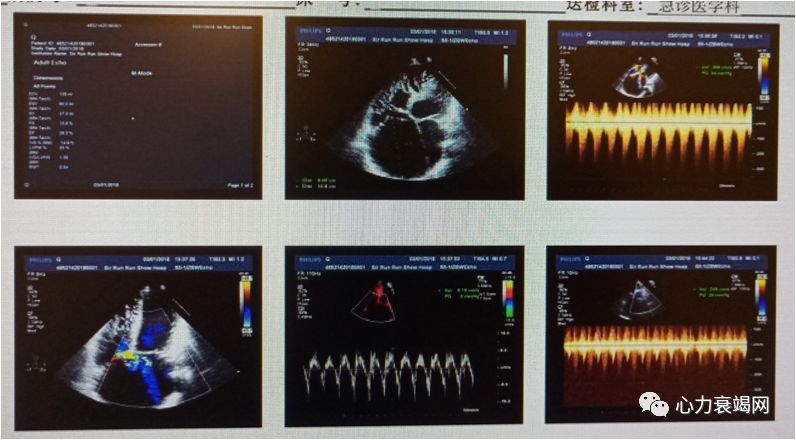

心超

Rastelli术后:

1、右室流出道轻中度狭窄,右心肥大,右室收缩功能减低,体循环回流障碍;2、左室收缩功能减低;

3、重度三尖瓣反流伴右室高压;

4、轻度二尖瓣反流;

5、心律不齐。